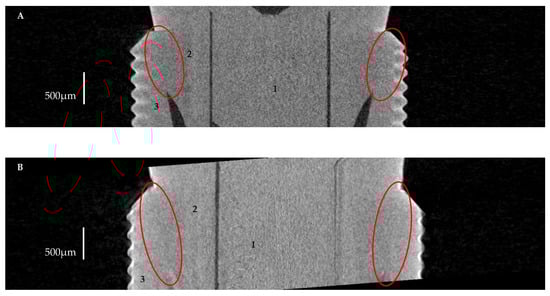

2.2.2. Volume of Microgap

3.2. The Volume of Microgaps